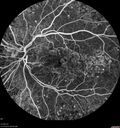

79 year old vision is in for a checkup with no visual complaints in the left eye. This is her better eye. VA 20/200 OD, 20/50 OS. 3 years ago she had a CRVO in the left eye. She is also diabetic for 20 years, has carotid insufficiency and anemia. Left eye shows CME. This was not treated and the vision improved to 20/40 over the next year although mild edema persisted.